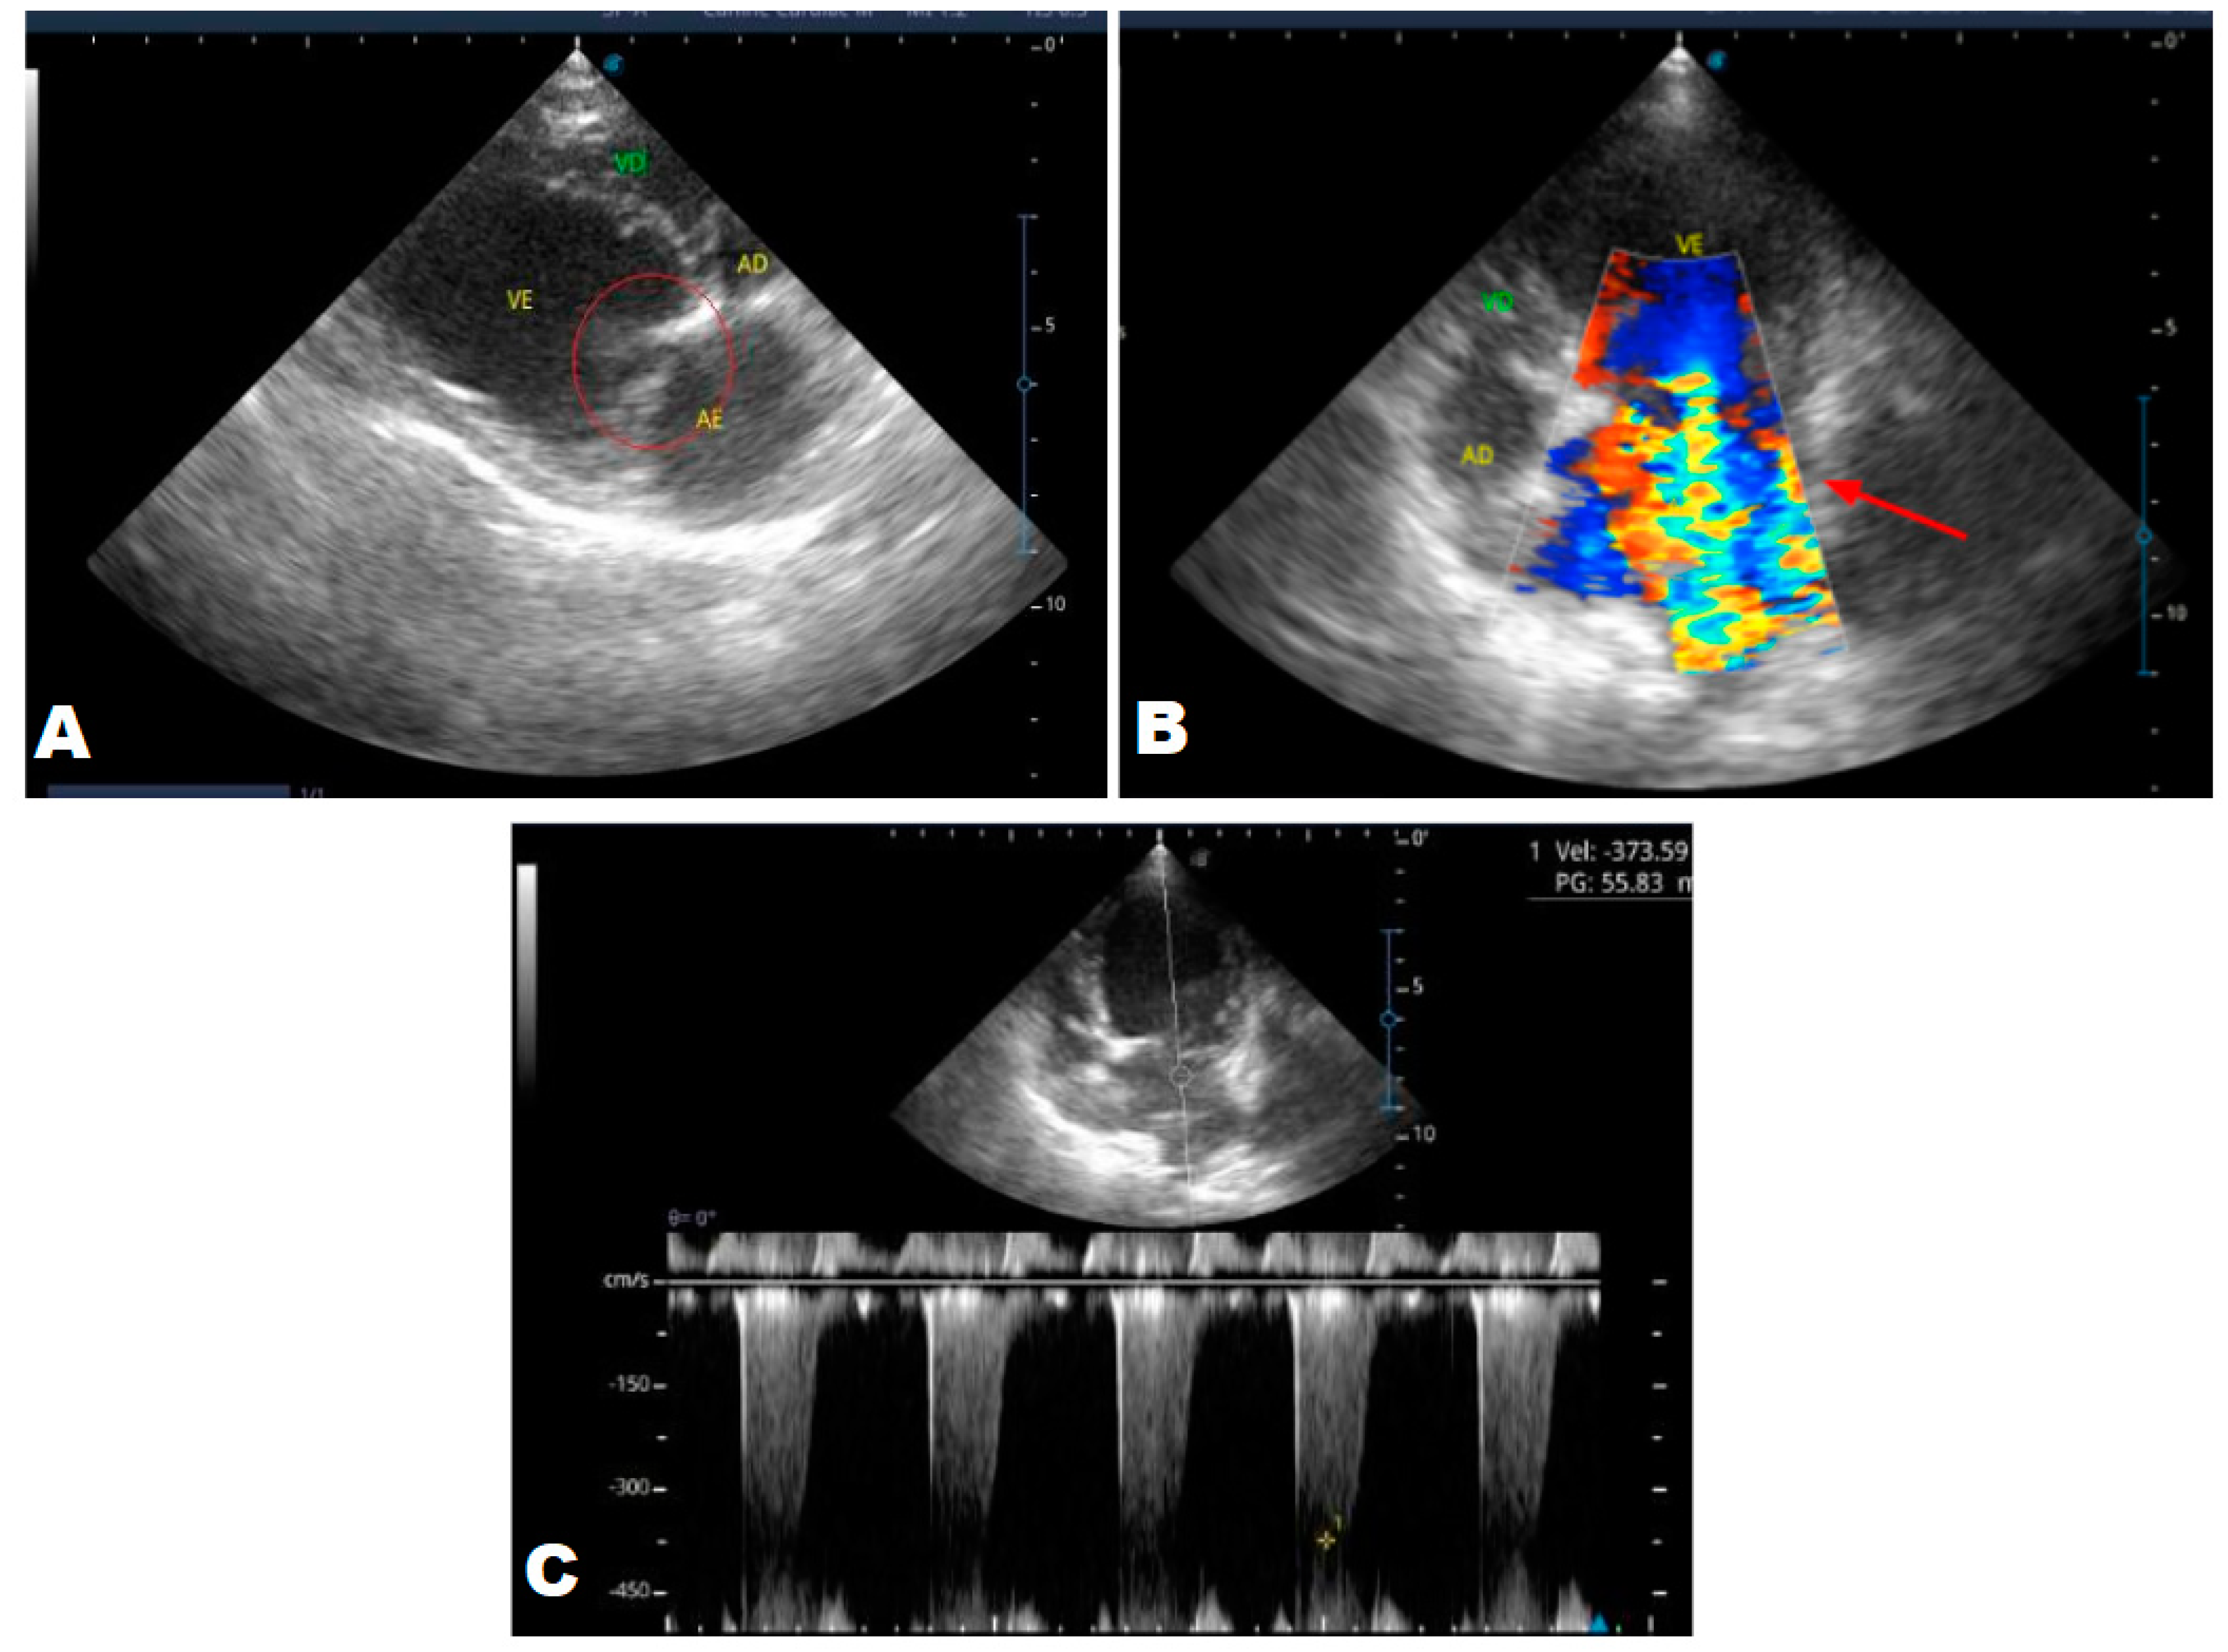

Figure 5. Echocardiogram (January/2023): observed increase in the left atrium and ventricle; thickened/degenerated/prolapsed mitral valve (A); observed in Doppler study, systolic turbulent flow within the left atrium characterizing severe mitral valve insufficiency (B). Hemodynamic assessment - Maximum velocity gradient mitral regurgitation: 3.74 m/s / 55.83 mmHg: Observed left ventricular diastolic dimension above normal limits, with normal systolic function parameters, characterizing systolic dysfunction; preserved diastolic function.

In 2023, the animal returned and repeated only the ECHO (Figure 5), where no significant changes were observed during this period, except for a structural change in the mitral valve, identifying a prolapse and increase in the left ventricular diastolic dimension, with systolic function parameters. normal, characterizing systolic dysfunction; diastolic function remained preserved.